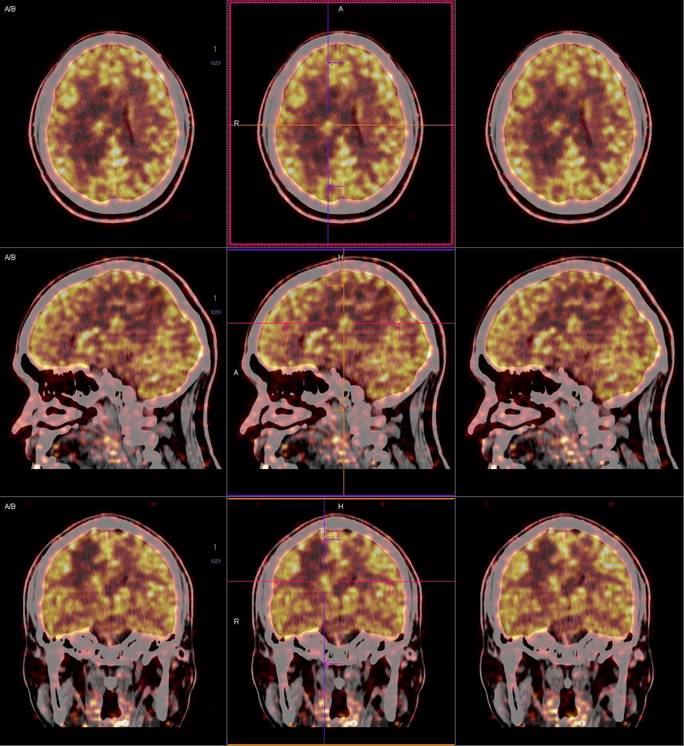

PET/CT影像圖

圖1

圖2

圖3

圖4

PET/CT檢查

影像診斷: 右側(cè)側(cè)腦室旁腦實(shí)質(zhì)內(nèi)結(jié)節(jié),代謝異常增高(SUVmax 12.13),伴瘤周水腫。

病理診斷:腦膜瘤二級(jí)

PET/CT鑒別診斷

正電子發(fā)射計(jì)算機(jī)斷層(positron emission tomography,PET)是一種分子成像技術(shù),PET 應(yīng)用 18F-FDG等顯像劑可顯示人體內(nèi)細(xì)胞、分子或者基因水平的生物學(xué)、病理學(xué)過(guò)程,進(jìn)一步實(shí)現(xiàn)疾病早期定量與定性診斷。PET/CT使形態(tài)影像學(xué)與功能影像學(xué)得到了良好的結(jié)合,更有利于對(duì)腦膜瘤進(jìn)行全面的評(píng)價(jià)。既往研究發(fā)現(xiàn),18F-DG PET/CT對(duì)診斷WHOⅠ、Ⅱ級(jí)腦膜瘤具有較高的敏感度,F(xiàn)DG攝取可用于評(píng)估腦膜瘤的腫瘤增殖情況,以此達(dá)到鑒別腦膜瘤的良、惡性的目的。有學(xué)者統(tǒng)計(jì),WHOⅡ、Ⅲ級(jí)與 WHOⅠ級(jí)的平均標(biāo)準(zhǔn)化攝取值(standardized uptake value,SUV)分別為 2.51 (1.36,3.66)和 0.42 (0.12,0.73),WHOⅡ、Ⅲ級(jí)腫瘤與正常組織比率(T/N比率)存在差異,WHOⅡ級(jí)腦膜瘤的 SUVmax和最大T/N比率顯著高于 WHOⅠ級(jí)腦膜瘤。SUV和T/N比率對(duì)高級(jí)別腦膜瘤的診斷有較高的特異度。

此例,PET/CT全身檢查不僅排除了轉(zhuǎn)移瘤的可能性,增高的SUV值無(wú)創(chuàng)地鑒別腦膜瘤的良惡性,充分體檢PET/CT大視野、形態(tài)與功能影像結(jié)合的優(yōu)勢(shì)。